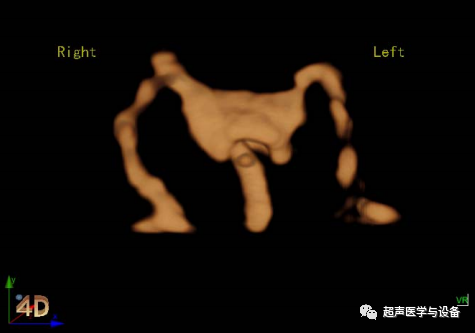

智真光影4D

妇产方面,智真光影4D技术突破更大的三维图像显示区,高效的预备状态裁剪线,通过对光源的控制,让

胎儿更形象生动,栩栩如生。